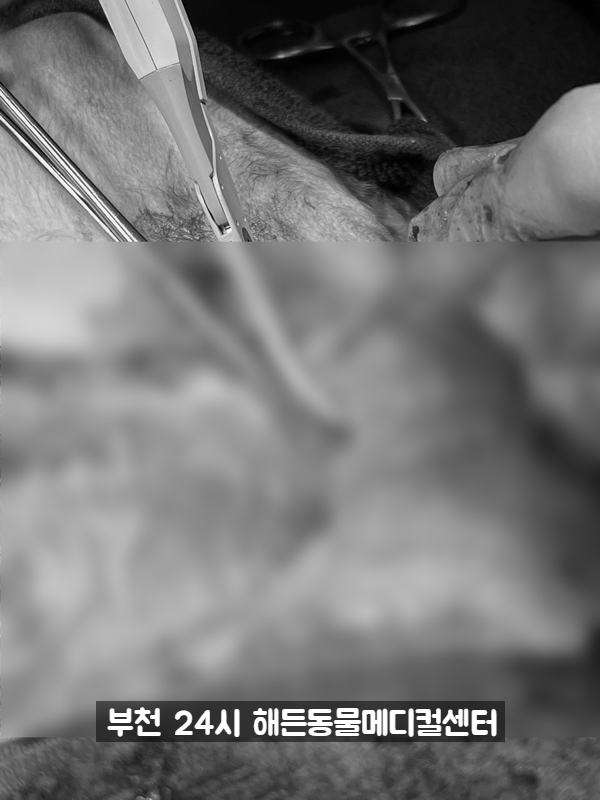

수술이 잘 됐어요.

자궁축농증 유선종양 전체 적출종양 등 3개의 큰 수술을 모두 끝냈습니다.